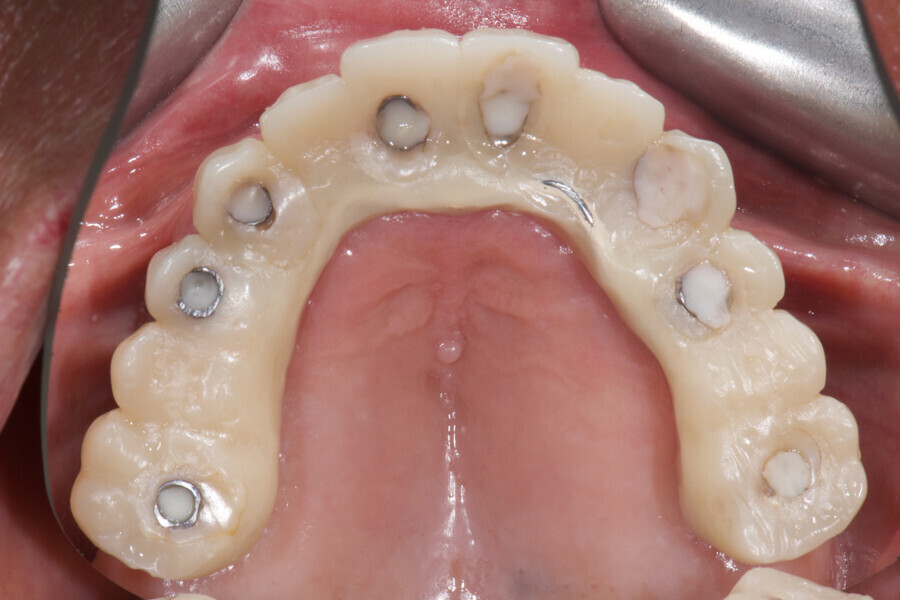

Novel digital workflow for full-arch rehabilitation

Fig. 2: Initial situation, occlusal view.

An 85-year-old partially edentulous patient was referred to our clinic for full-arch rehabilitation of the maxilla. The patient was in good general health and a non-smoker. His primary complaints included difficulty in chewing, maxillary pain and occasional halitosis. Clinical and radiographic evaluation revealed a short-span fixed metal–ceramic prosthesis supported by seven anterior maxillary teeth. The prosthesis had debonded, and four of the abutment teeth were structurally compromised. The remaining three showed varying degrees of caries and periodontal problems. A diagnosis of failing dentition was established (Figs. 1 & 2).

At the initial visit, digital impressions were captured using the Medit i700 scanner to document the residual teeth, soft tissue, existing prosthesis and opposing arch. The occlusal records were obtained at the current vertical dimension of occlusion and in centric relation. Mandibular movements were recorded with the zebris JMA jaw registration system (zebris Medical). Intra- and extra-oral photographs were also taken. A virtual diagnostic wax-up and a digital smile simulation were created based on these records (Smile Creator, exocad). Finally, eight implants were planned (Figs. 3 & 4) according to the new wax-up (exoplan 3.1, exocad), and both a surgical guide and a metal-reinforced temporary prosthesis were fabricated in advance (Figs. 5–7).